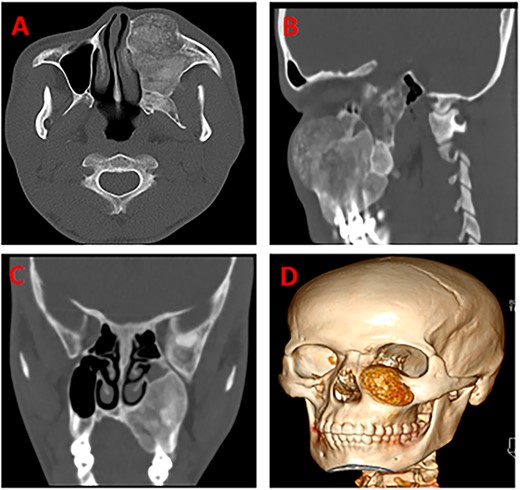

A 26-year-old male patient reported to the oral and maxillofacial unit of our institution with a chief complaint of a painless, slow-growing mass on the left side of his maxilla for three years. The lesion started as a small swelling that progressively increased in size with time, with no relieving or aggravating factors reported. There was no history of preceding trauma, loss of weight, or night sweat reported to be associated with the new growth. The patient was a non-smoker, with a healthy general condition. On examination, the patient did not have any systemic problems. There was a facial asymmetry due to the mass on his midface whose measurements were 6 by 7 cm, extending from the ala of the nose right side to the body of the zygoma bone on the same side, anterior posterior, zygomatic arch to the angle of the mouth right side, superior inferior direction (Fig. 1A). There was no enlargement of lymph nodes. Speech and swallowing remained undisturbed. On examination of the oral cavity, the mass on the maxilla, which was hard in consistency, non-tender, and measuring about 4 cm by 6 cm in its greatest dimensions, was appreciated (Fig. 1B). A clinical diagnosis of ossifying fibroma of the maxilla was considered, with a differential diagnosis of fibrous dysplasia. A CT scan of the head highlighted a well-defined expansile radiolulency mass with radiopaque features. The mass was causing bone erosion and opacification (Fig. 2A–D). Histopathology of an incisional biopsy demonstrated a benign fibro-osseous lesion composed of diffuse hyperchromatic stromal fibroblastic cell proliferation, without atypia or mitoses. The matrix was mineralized with woven and lamellar bone deposits, or cementum-like calcifications distributed throughout the lesion (Fig. 3). The diagnosis of maxillary OF was confirmed, and the treatment was scheduled.

CT scans of the head highlighting a well-defined expansile radiolulency mass with radiopaque features (A), the mass is causing bone erosion (B), and opacification (C), a 3D of the tumor (D), respectively.